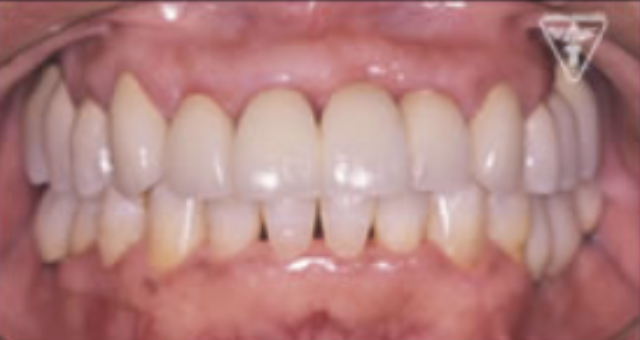

治療後

治療前後の比較

治療前